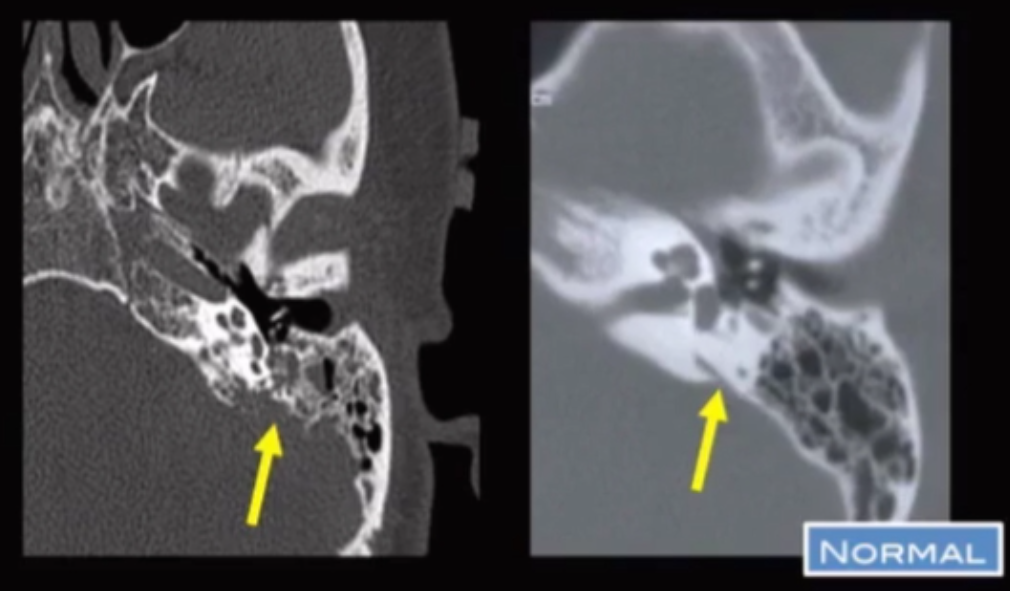

Endolymph sac Tumor

• Typically papillary endolymphatic sac cystadenoma

• Enhances

• Internal calcifications

• Looks like bone has been eaten away at

• Yellow arrow points to vestibular aqueduct

• Strongly associated with VHL (may be bilateral)